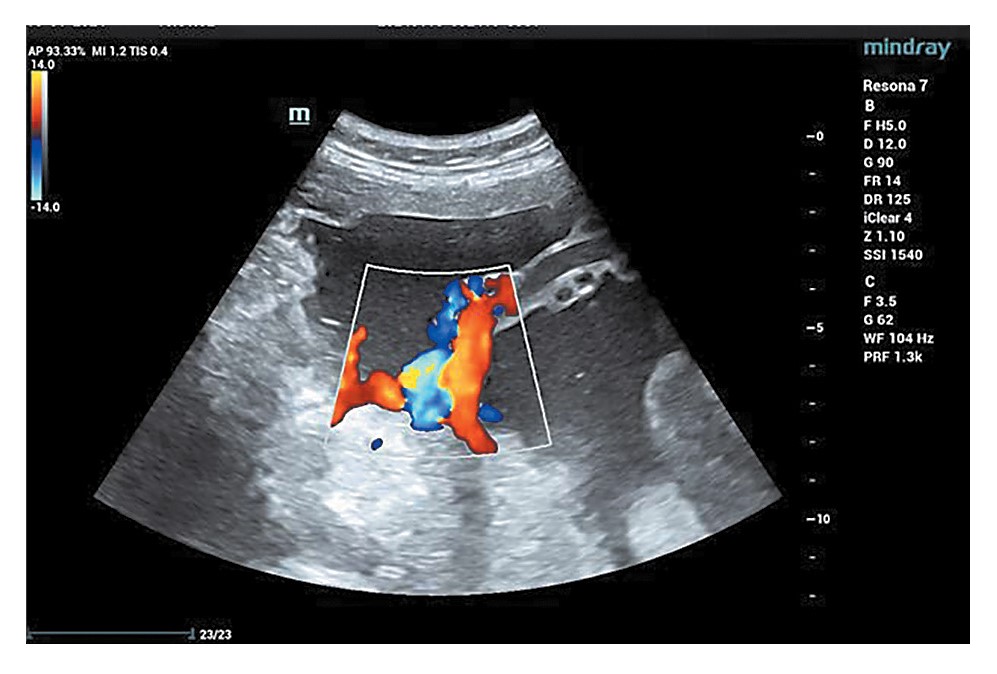

В большинстве наблюдений отмечены различные сочетания приведенных УЗИ-признаков (рис. 1–3).

Рис. 2. Эхограмма. ВУИ. Беременность 27 нед. Изменение извитости пуповины (фрагмент гипоизвитости пуповины).

Fig. 2. Sonogram. IUI. 27 weeks of gestation. Change in umbilical cord tortuosity (fragment of reduced tortuosity of the umbilical cord).